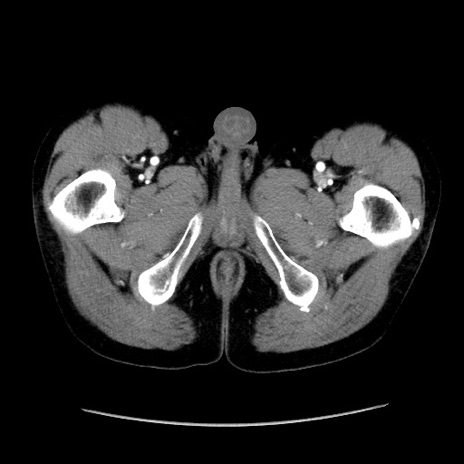

症例37(横断像)

【症例】40歳代 男性

【主訴】腹痛

【現病歴】4時間ほど前に電車に乗車中に臍部上より腹痛出現。徐々に増悪し起立困難となり、救急外来受診。生ものは数日食べていない。今朝お雑煮を食べた。

【身体所見】BT 36.8℃、BP 117/84mmHg、HR 91/min、SpO2 97%、苦悶様、腹部:臍上部広範囲圧痛あり、反跳痛±

【データ】WBC 8100、CRP 0.03